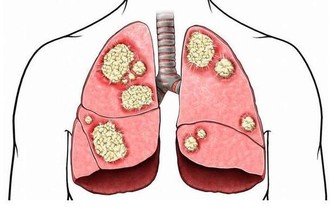

6. 一些嚴重的疾病,例如白塞氏病和口腔內的惡性腫瘤,此時往往遷延不愈,且可能伴隨全身其它症狀。